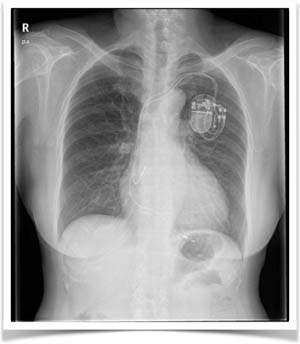

입원 시 환자의 심전도는 <그림 1>과 같았다. 환자는 입원후 지속적으로 심장박동에 대한 검사를 실시해 <그림2>와 같은 이상소견을 확인할 수 있었다. 환자는 서맥이 있을 때 어지러움을 호소했다. 환자는 검사결과 동기능부전증후군 진단을 받고 영구형 인공심박기 시술을 받았다.<그림3>

심박조율기란 심장 리듬의 문제를 감지해 심장이 규칙적으로 제 시간에 박동하도록 자체의 전기 자극을 보내는 장치로 내부에 전자장치와 배터리로 구성돼 있으며 간단한 수술을 통해 상흉부 혹은 복부에 이식할 수 있다. 주로 좌측상흉부에 이식한다. 또한 전극선을 이용해 심박동기와 심장 근육 사이를 연결해 전기 자극을 심장에 전달하기도 하고, 심장의 리듬을 심박동기가 감지하도록 해 적절한 시간에 전기 자극을 전달할 수 있게 도움을 준다.